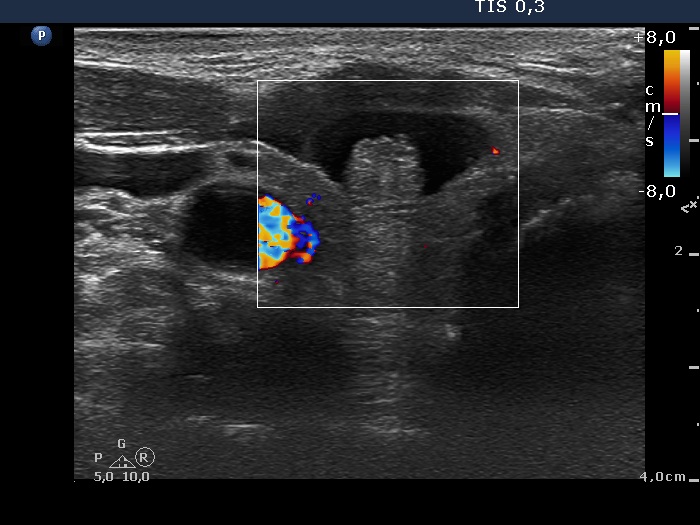

Ultrasonography. The thyroid was echonormal. There was a peripheral-type cystic nodule in the ventral part of the right lobe. The lesion had non-specific echogenic granulations. The lesion did not display vascularization on Doppler mode.